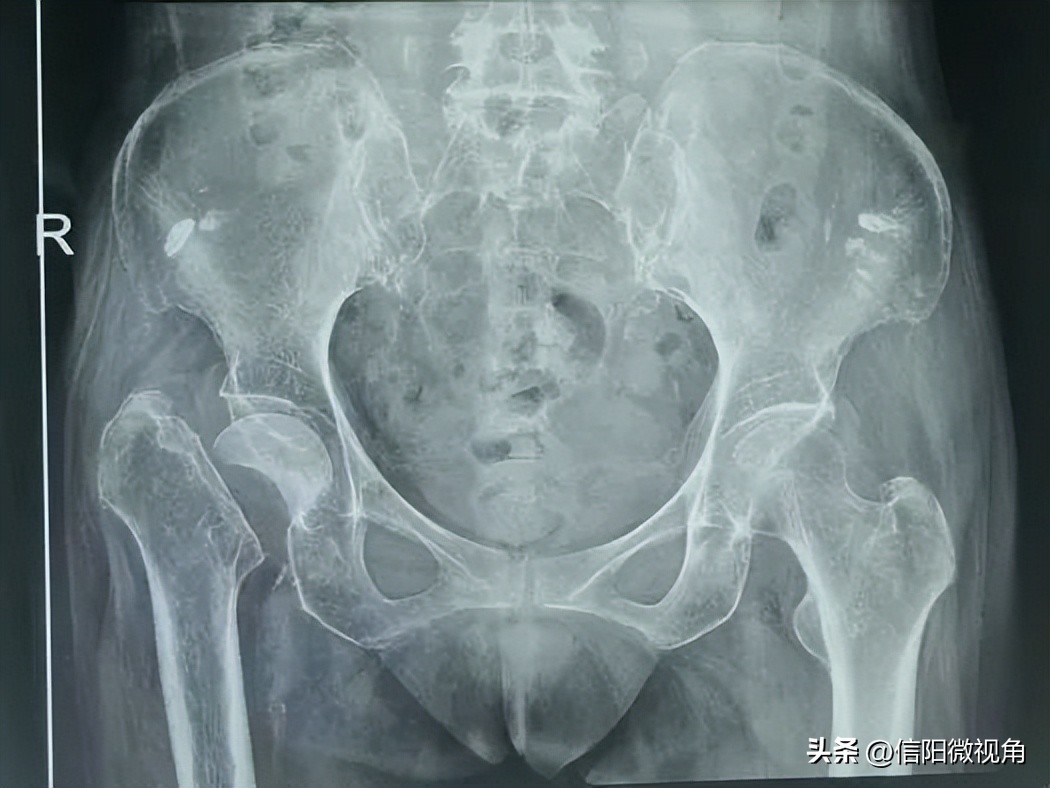

66岁的张阿姨7年前在武汉进行了心脏移植手术,术后一个月因脑梗摔倒致右侧股骨颈骨折,心脏术后需抗排异治疗,再加上脑梗后右下肢偏瘫并患有高血压、糖尿病多年,骨折一直未能处理,常年卧床,不能坐立。

术前